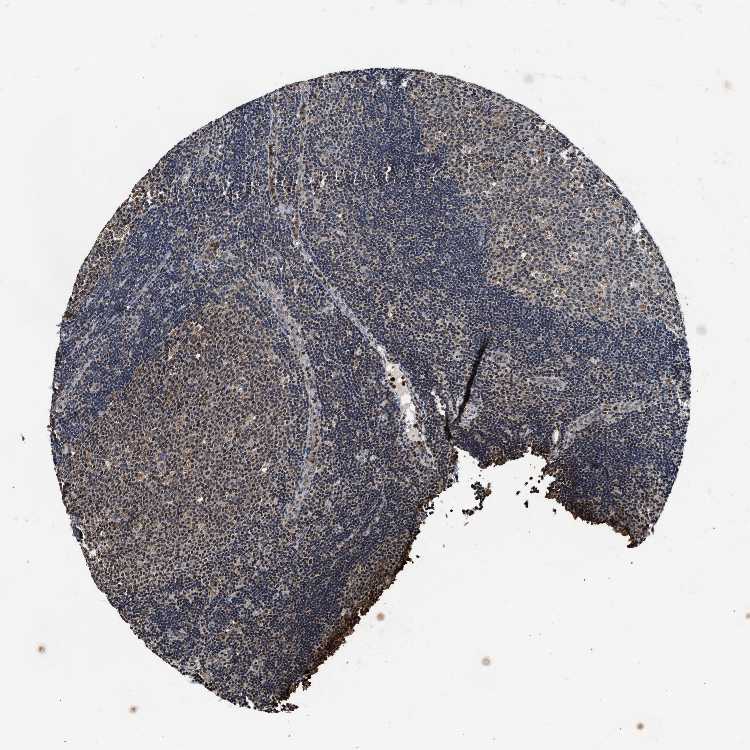

TISSUE PRIMARY DATA LYMPH NODE Show tissue menu

Lymph node

LYMPH NODE - Antibody stainingi

Antibody staining in the annotated cell types in the current human tissue is reported as not detected, low, medium, or high, based on conventional immunohistochemistry profiling in selected tissues. This score is based on the combination of the staining intensity and fraction of stained cells.

Each image is clickable and will lead to virtual microscopy that enables deeper exploration of all samples and also displays staining intensity scores, fraction scores and subcellular localization as well as patient and tissue information for each sample.

Antibody HPA021192Antibody HPA021195Antibody HPA028759Antibody CAB021094

Germinal center cells MediumNot detectedNot detectedMedium

Non-germinal center cells MediumMediumNot detectedLow